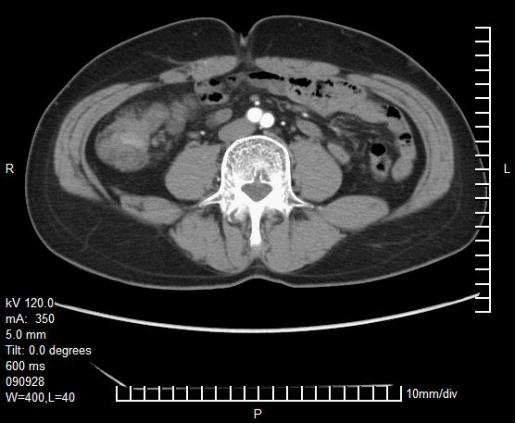

影像学检查

入院时胸、腹、盆腔等影像学检查及CT/MRI片子

患者男性,56岁,确诊右半结肠癌伴肝脏多发转移,确诊时临床危险评分(CRS)4分(具有同时性肝转移、多个转移灶、最大病灶长径>5cm、CEA>200ng/ml)属于高危患者[1]。按照ESMO推荐的对于结肠癌肝转移患者的评估标准该患者属于技术上难切除,预后差的患者,应该选取最佳全身治疗进行转化治疗[2, 3]。患者并未出现梗阻、明显出血、穿孔或其他原发肿瘤引起的症状,因此按照NCCN指南推荐全身治疗而不建议初始切除原发灶[4]。患者年轻、一般情况可,原发灶位于右半结肠,且其KRAS基因为突变型,因此推荐选择三药联合化疗(FOLFOXIRI),如患者经济上可以承受也可考虑三药或双药(FOLFOX或FOLFIRI)联合贝伐单抗[5, 6]。关于右半结肠癌的一线治疗推荐,2017版NCCN指南明确指出不考虑使用EGFR抗体;而ESMO指南对于RAS野生型、Braf野生型患者,当以肿瘤减灭为目的时首选两药联合+EGFR抗体,次选三药联合或不联合贝伐单抗。针对一线化疗对比化疗联合西妥昔单抗的左右半分析,共有两项Ⅲ期临床研究的回顾性分析结果和一项中山大学肿瘤防治中心的回顾性研究结果,在CRYSTAL、TAILOR和我们的研究中都显示化疗联合西妥昔单抗对比单纯化疗有效率、PFS和OS均未呈现显著提高[7, 8]。另外两项头对头比较双药联合贝伐单抗或西妥昔单抗的临床研究FIRE3和80405都显示两者在有效率方面无显著的差别[9]。因此如果该患者为RAS野生型仍不建议首选EGFR抗体治疗。

2程化疗后展示的患者肝脏CT无明显改变,评价为PD的原因不明。若患者因肝脏或其他部位出现新发病灶出现了病情进展,可考虑二线采用FOLFIRI联合贝伐单抗,4程化疗后肝脏病灶明显减少、缩小,评价为PR。因贝伐单抗使用后需暂停6周以上才能进行手术,因治疗间隔太长,建议该患者在停用贝伐单抗期间进行FOLFIRI方案化疗2至3疗程。手术切除原发灶和肝转移灶,病理已确认。其后患者进行了术后辅助化疗4程,患者术前行化疗4程,仅出现Ⅱ度骨髓抑制,根据NCCN指南术后可建议其行8程FOLFIRI方案或2-3程FOLFIRI方案加6-5程FOLFIRI联合贝伐单抗方案化疗,达到共6个月的围手术期化疗。